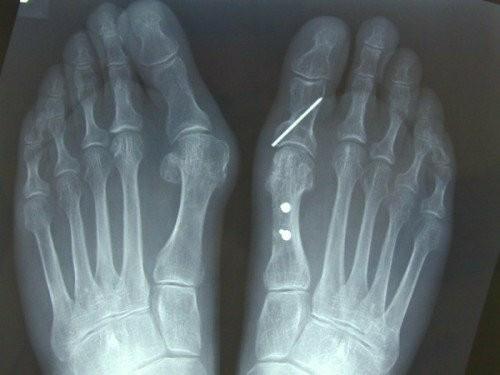

(A)拇外翻角和(B)第1-2跖骨角的测量可以反映拇外翻畸形的严重程度。

拇外翻角:第一跖骨轴与第一近端指骨轴之间。

x线片通过观察第一跖骨和近节趾骨的中轴线之间形成的角度来确定拇外翻的存在。如果角度大于15度,则诊断为拇外翻。45-50°的角度被认为是严重的。同时还应考虑第一节MTP关节内的籽骨移位程度和骨关节炎程度的变化。